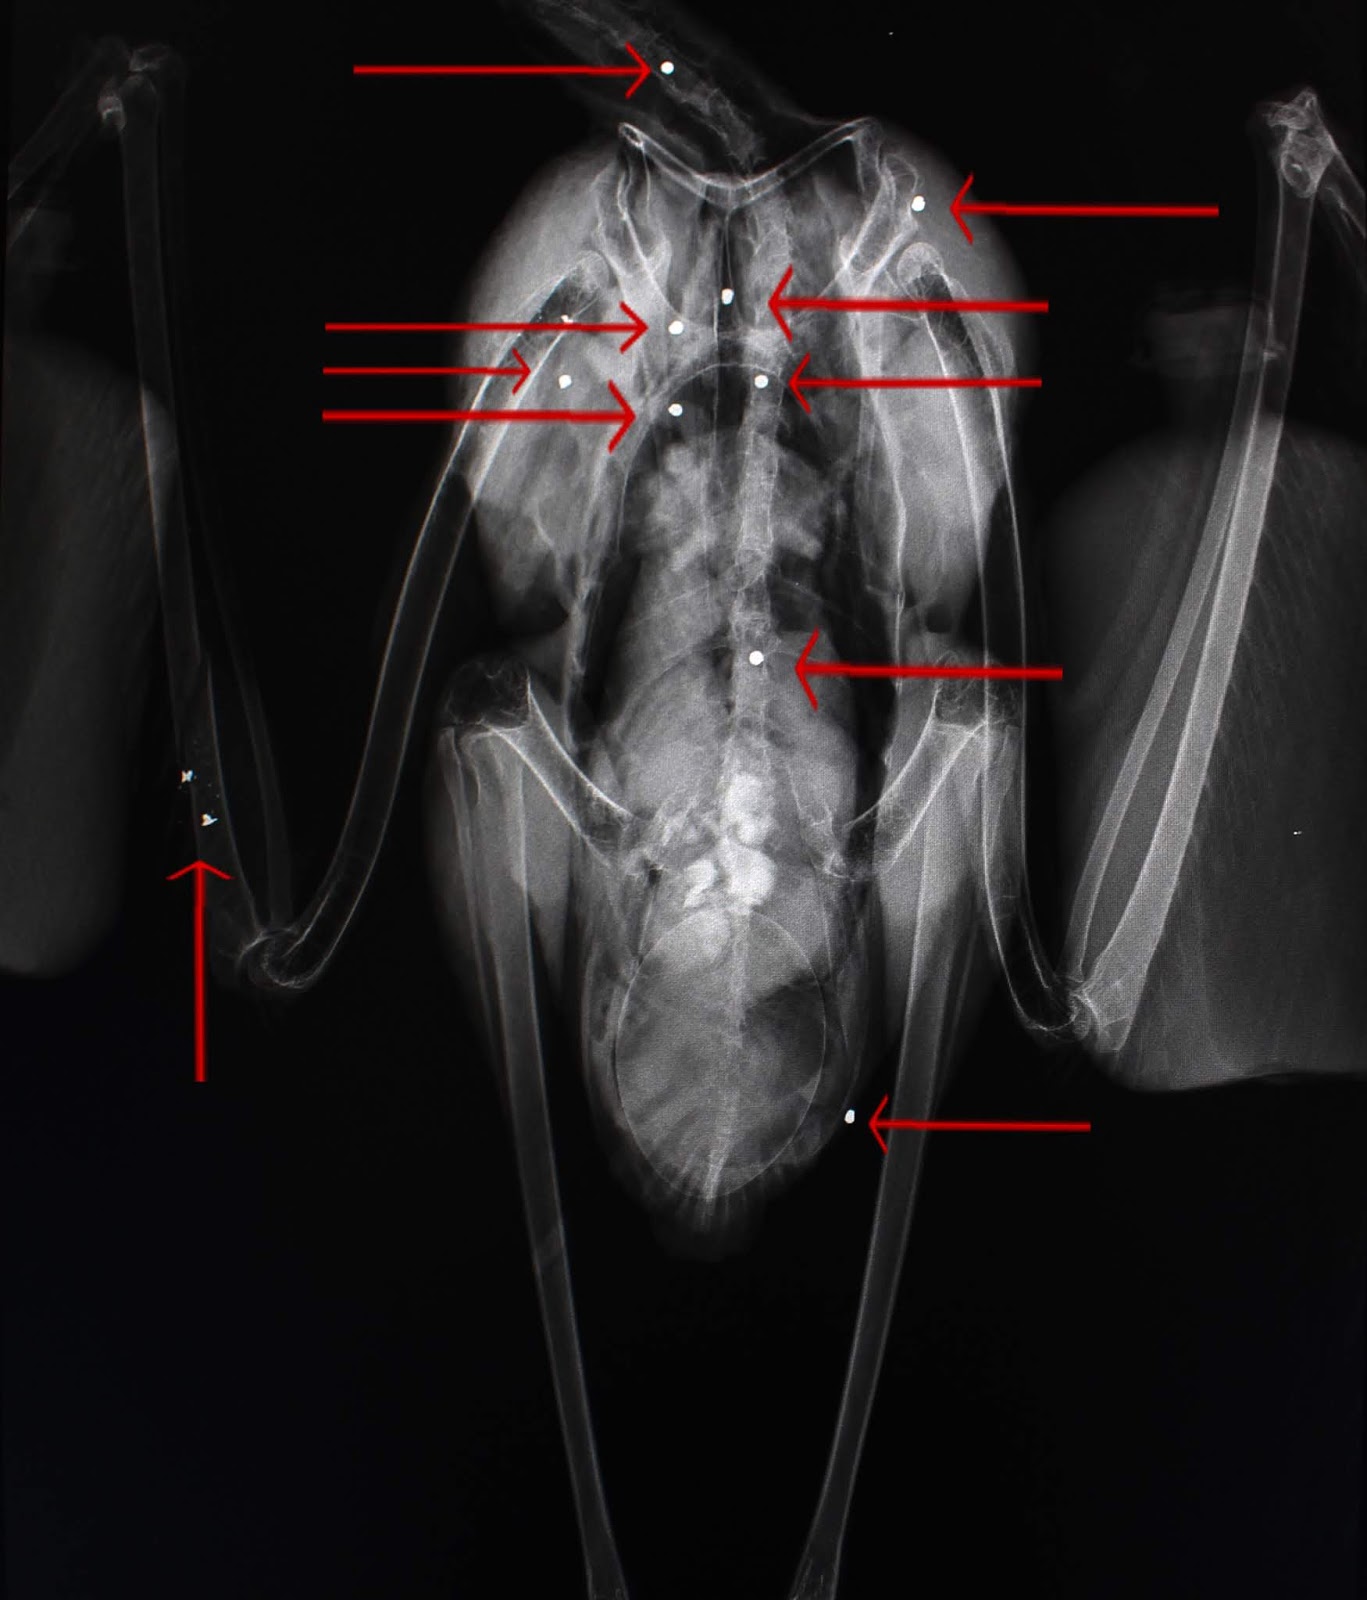

O passado Sábado Livre foi o culminar de quase 2 meses de recuperação para a cegonha-branca (Ciconia ciconia) que ingressou no RIAS com 10 chumbos no corpo.

Relembramos que a cegonha apresentava um ovo no interior, e que infelizmente não eclodiu, provavelmente devido a todo o stress a que a progenitora esteve sujeita.